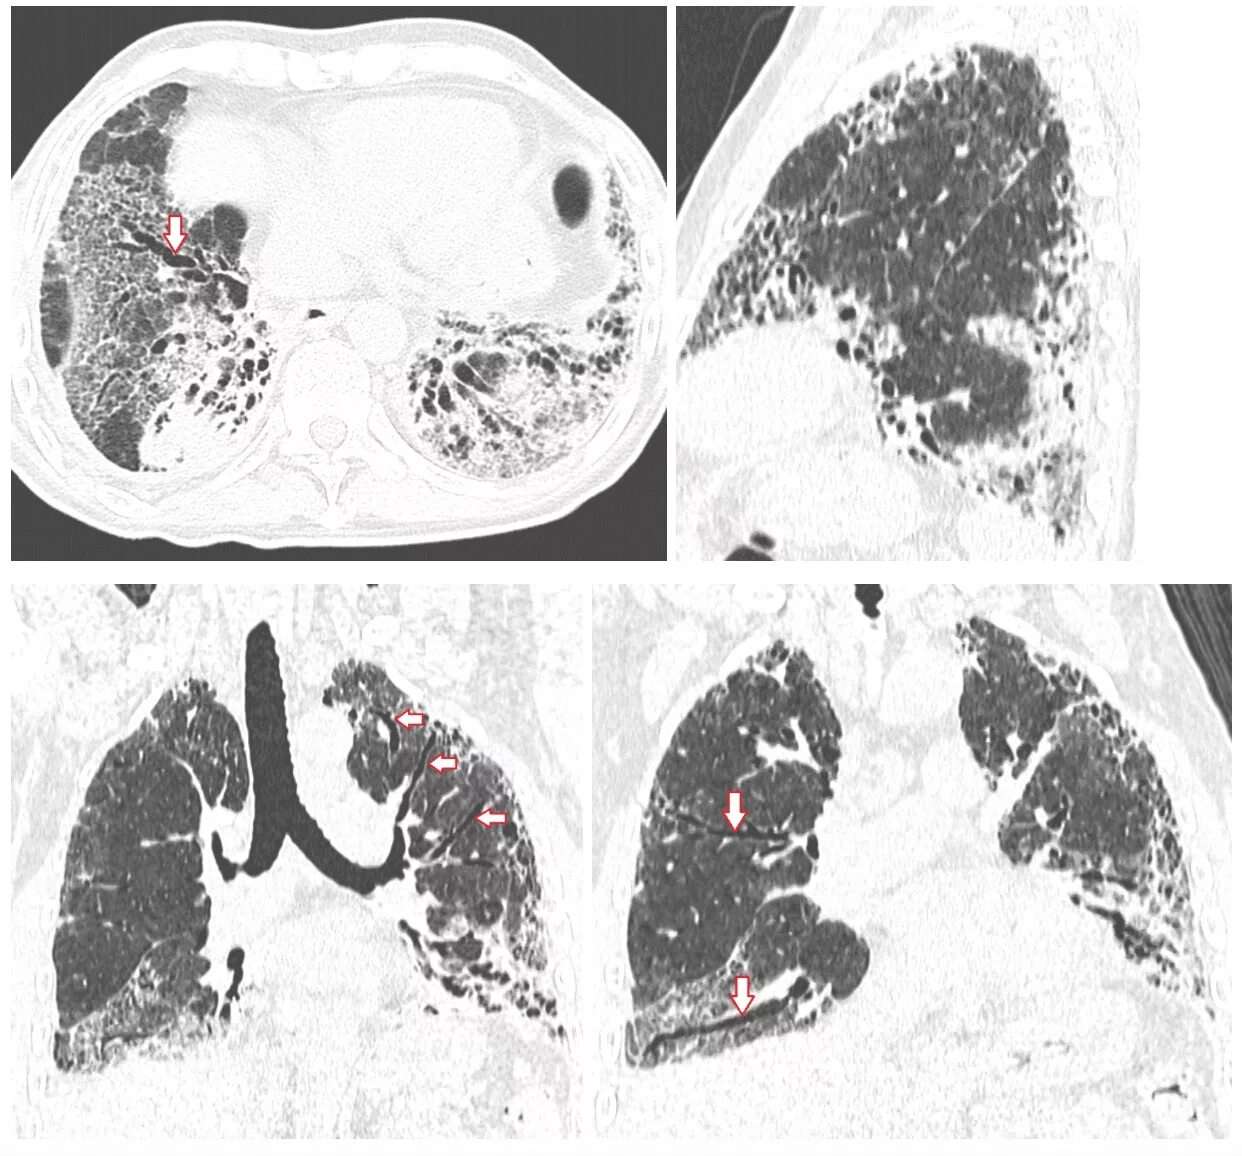

Заболевание кт